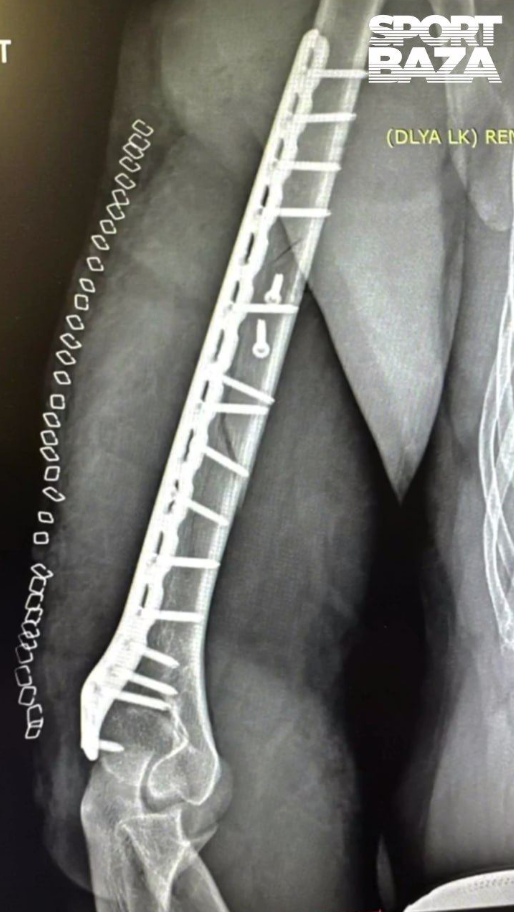

В пылу игры он перелетел через сетку и приземлился так неудачно, что получил двойной перелом плеча со смещением. Врачам пришлось собирать кость буквально по кусочкам: в операционной плечо укрепили пластиной на 17 (!) болтах. Теперь о возвращении на корт можно забыть на несколько месяцев - впереди долгое восстановление.